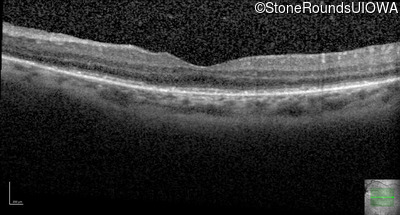

Optical Coherence Tomography - Right - 20/50 -1

Exemplar / OCT Stack